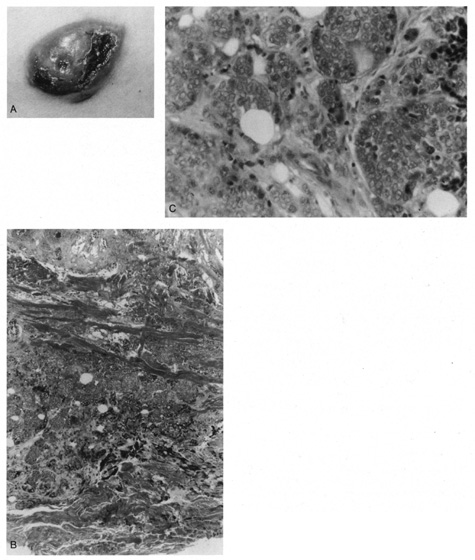

Pilomatrixoma

Pilomatrixoma, also referred to as Malherbe's calcifying epithelioma, is a cyst derived from the hair matrix that forms the hair. It is often a solitary lesion and most commonly occurs on the face. Most pilomatrixomas occur in the first two decades of life and, if superficially located, produce a blue-red skin discoloration. Excision is curative.

Histologically, pilomatrixomas show two types of cells in variable proportions: a basophilic cell with a dark basophilic nucleus and scanty cytoplasm and a “shadow cell,“ which has an unstained central nucleus and faintly eosinophilic cytoplasm (Fig. 23). There may be an abrupt or gradual transition between the two cells, and few or no basophilic cells may be seen in “old“ lesions. Calcification of pilomatrixoma is frequent and may occur within the shadow cells or in the stroma. The stroma usually is fibrotic and contains a foreign body reaction. Ossification also can occur occasionally.

Fig. 23. Pilomatrixoma—A. Low-power photomicrograph demonstrating immature bone formation and proliferation of epithelial cells (hematoxylin and eosin stain). B. Higher-power view showing an area of calcification within the tumor (ematoxylin and eosin stain). C. High-power photomicrograph showing the transition from basophilic epithelial cells (upper left) to “shadow cells“ in the lower right (hematoxylin and eosin stain). (Photos courtesy of William Morris, M.D.)